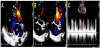

A 34-year-old woman visited our outpatient clinic due to dyspnea and chest discomfort newly developed one month ago. The symptoms progressively worsened during a several months’ period. Dyspnea was aggravated by exertion. Substernal chest pain was intermittent and of squeezing nature and it was not related to exercise. She had been heard about a hole between cardiac chambers when she was young; however, she did not remember the correct diagnosis. She had no other significant prior medical history except scoliosis. She was not a smoker and had no family history of heart disease. On initial examination, her general condition was good with blood pressure of 120/50 mmHg, and pulse rate of 77 per minute. She was afebrile, and there was no jugular venous distension or peripheral edema. There was a loud continuous murmur along with the left parasternal border line accompanied by a thrill. There were no other remarkable findings in chest and heart examinations. Electrocardiogram (ECG) showed nonspecific ST-T segment changes with normal axis (Figure 1A). Chest X-ray showed mild cardiomegaly and curved thoracic vertebrae (Figure 1B). There were no specific findings in blood tests including cardiac enzyme, inflammatory markers, rapid plasma regain test for syphilis and human immunodeficiency virus test. Transthoracic echocardiography (TTE) revealed normal size and function of both left and right ventricles (LV and RV). Color flow and pulsed wave Doppler identified a jet flow from the aorta to RV, at the level of the aortic root, seen during both systole and diastole (Figure 2 and Videos 1 and 2). There was no valvular stenosis or regurgitation of the aortic valve (AV). Rupture of SVA was suspected. However, the aneurysmal sac was not clearly defined by TTE, and other cause of intra-cardiac shunting, such as ventricular septal defect (VSD), could not be ruled out. Therefore, ECG-gated computed tomographic (CT) coronary angiography was performed to obtain information on additional cardiac pathology and relation to the coronary arteries. CT scan revealed a ring-like structure originating from the right coronary sinus of AV protruding to the RV. The ostium of the right coronary artery was not involved by the aneurysm, and there was no significant stenosis of coronary arteries (Figure 3A). Extravasation of the radiocontrast agent from the SVA to the RV was also seen on CT scan (Figure 3B). Based on these findings, the patient was scheduled for surgery. Immediately before surgery, transesophageal echocardiography (TEE) was carried out for surgical planning. The findings of TEE were concordant with those of aforementioned cardiac CT. TEE revealed a protruding aneurysmal sac with shunting from the right coronary sinus to RV (Figure 4 and Video 3). Invasive cardiac catheterization was not performed. Surgical findings confirmed a large aneurysm with a defect at right coronary sinus of the AV. There was no other combined cardiac pathology. Resection of the aneurysmal sac and repair of the aortic root using an autologous pericardial patch was performed. After surgery, TTE no longer showed abnormal shunt flow at the aortic root except minimal valvular regurgitation of the AV (Figure 5 and Video 4). She has been doing well without chest symptoms after surgery.